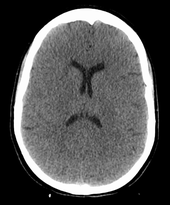

The cause of death in hanging depends on the conditions related to the event. When the body is released from a relatively high position, the major cause of death is severe trauma to the upper cervical spine. The injuries produced are highly variable. One study showed that only a small minority of a series of judicial hangings produced fractures to the cervical spine (6 out of 34 cases studied), with half of these fractures (3 out of 34) being the classic "hangman's fracture" (bilateral fractures of the pars interarticularis of the C2 vertebra).[22] The location of the knot of the hanging rope is a major factor in determining the mechanics of cervical spine injury, with a submental knot (hangman's knot under the chin) being the only location capable of producing the sudden, straightforward hyperextension injury that causes the classic "hangman's fracture".

The side, or subaural knot, has been shown to produce other, more complex injuries, with one thoroughly studied case producing only ligamentous injuries to the cervical spine and bilateral vertebral artery disruptions, but no major vertebral fractures or crush injuries to the spinal cord.[24] Death from a "hangman's fracture" occurs mainly when the applied force is severe enough to also cause a severe subluxation of the C2 and C3 vertebra that crushes the spinal cord and/or disrupts the vertebral arteries. Hangman's fractures from other hyperextension injuries (the most common being unrestrained motor vehicle accidents and falls or diving injuries where the face or chin suddenly strike an immovable object) are frequently survivable if the applied force does not cause a severe subluxation of C2 on C3.